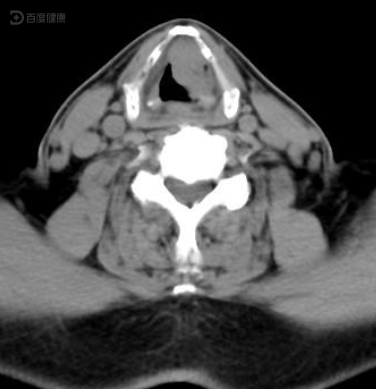

ct诊断:右喉癌(声门上型),伴右颈淋巴结转移.

喉癌的影像学诊断_声门